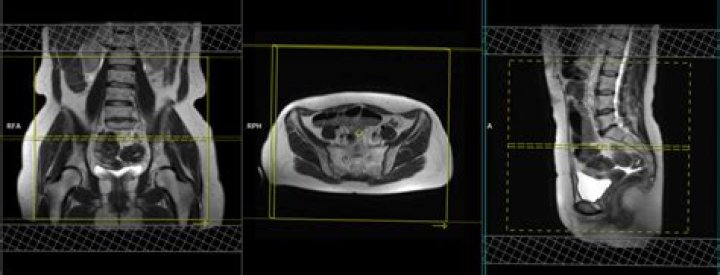

Pelvic magnetic resonance imaging (MRI) is one imaging technique that doctors may use to help diagnose endometriosis. The test provides a picture of organ...